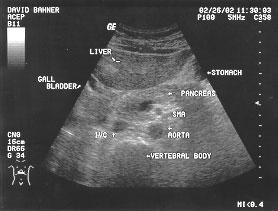

Aorta - suprarenal (labeled)